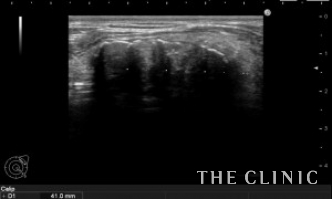

エコー所見です。

しこりを崩したためか、石灰化したカプセルが扁平に見えます。